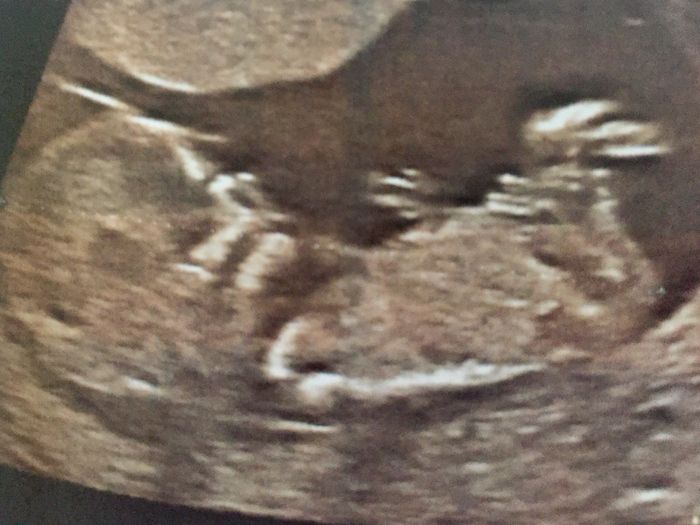

Buona sera, sono alla tredicesima settimana, ho scoperto da pochi giorni la teoria nub, secondo la quale si riuscirebbe a stabilire il sesso del nascituro. Chi di voi ha avuto già un esperienza del genere? E se qualcuna è in grado, vedendo l'eco , di...